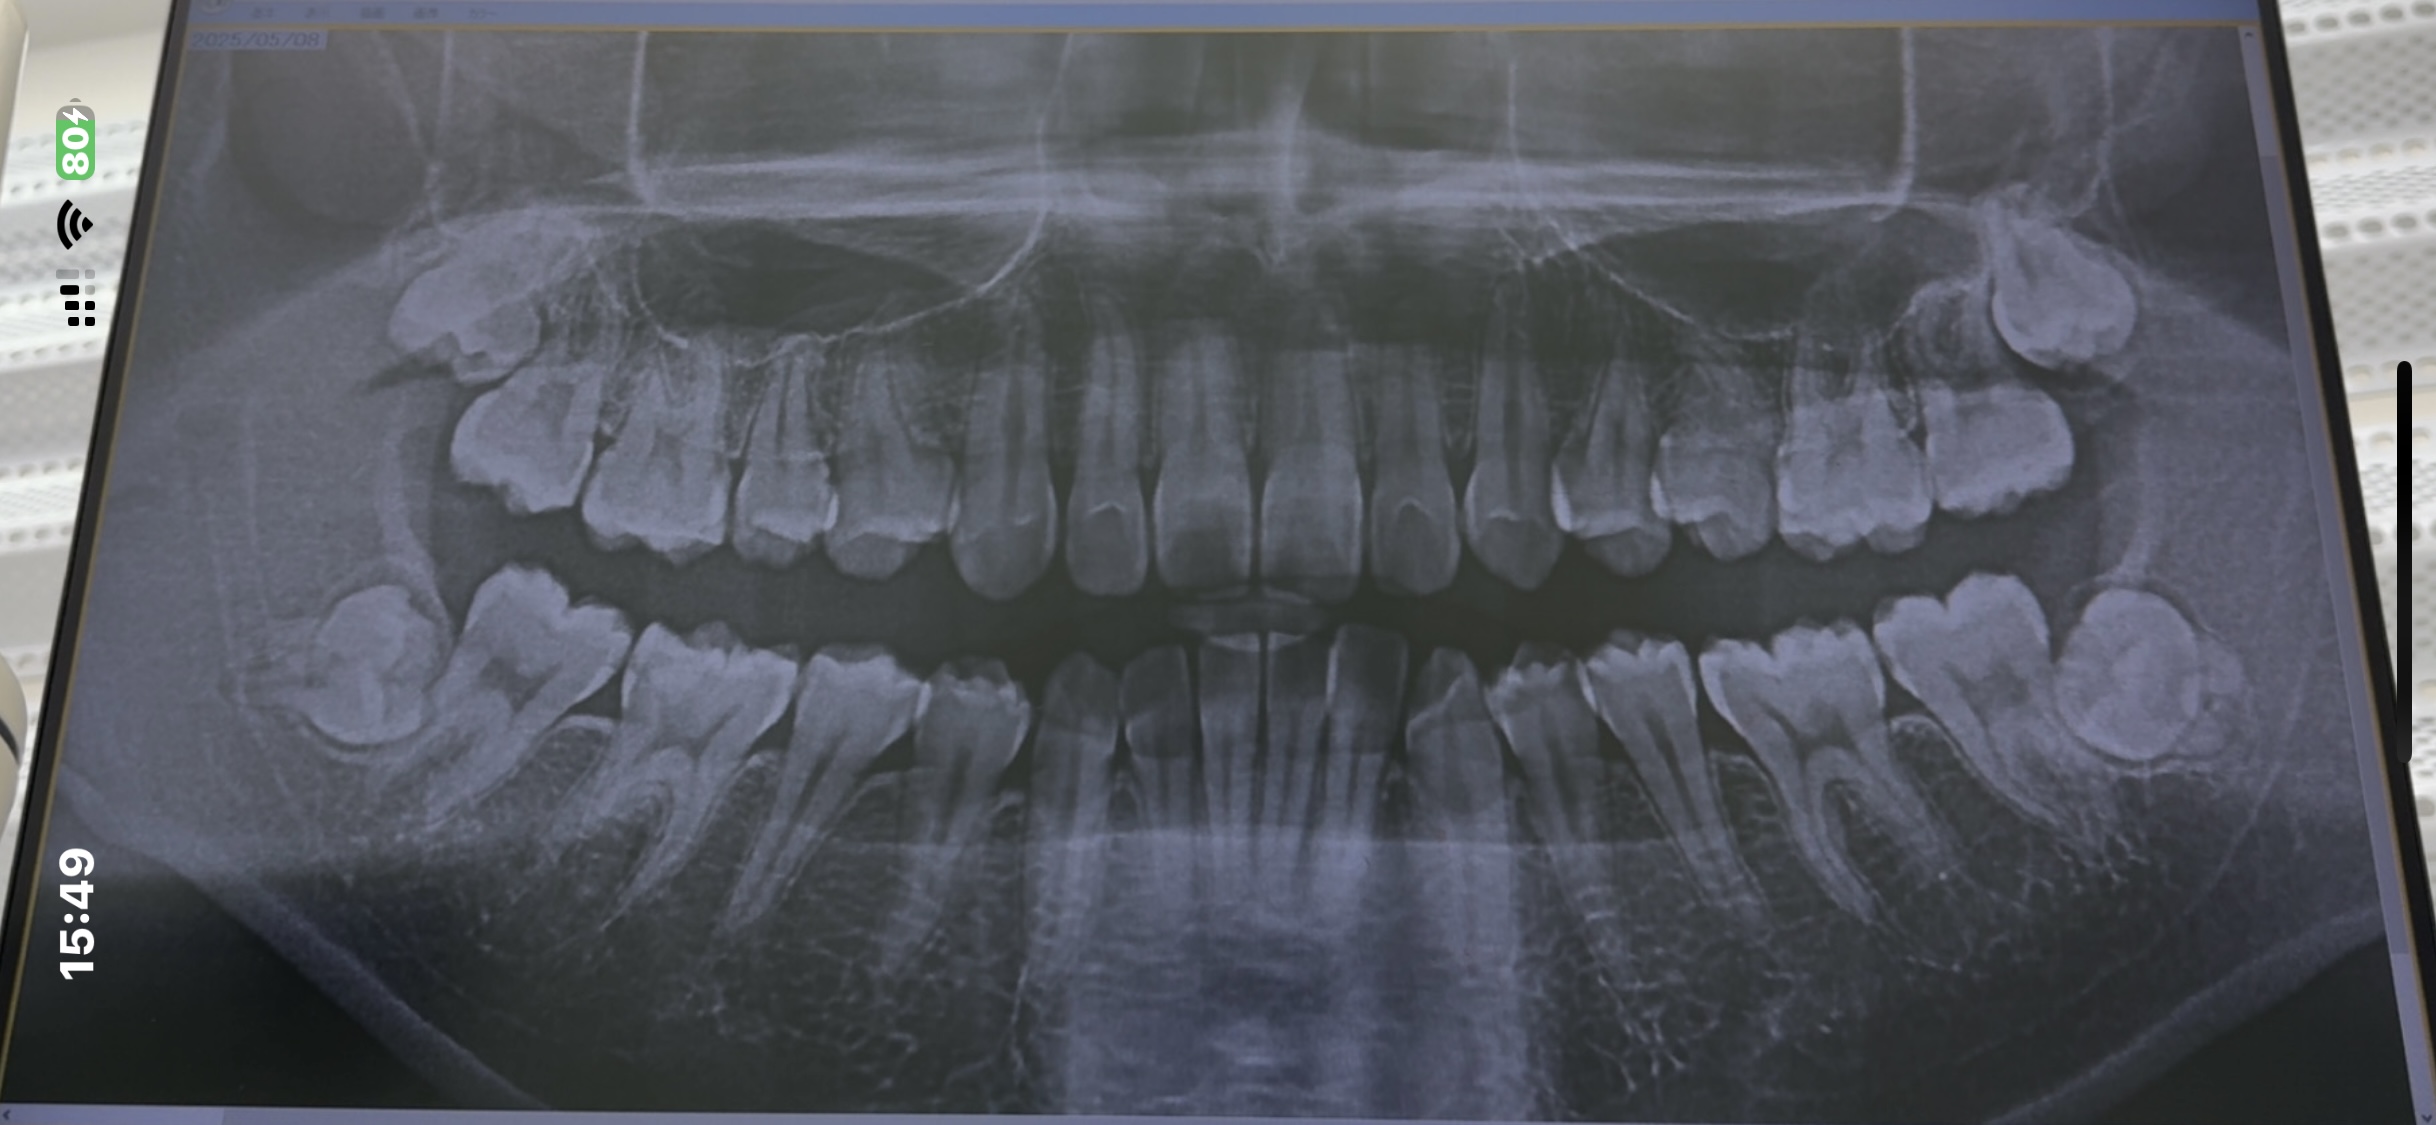

抜歯は当院では日々この様な抜歯ばかり行っておりますので大した事有りません。